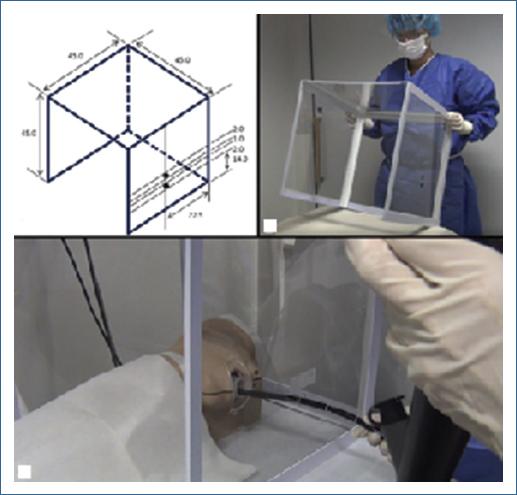

- Cámara de aerosol. La contención o redireccionamiento del aerosol se da por cuatro láminas de policarbonato con 4 mm de espesor, que se disponen como tres paredes y un techo. Dos aperturas paralelas en la lámina superior del paciente, para permitir intubar o auxiliar con el endoscopio. Una apertura en cada lámina lateral cumple la finalidad del paso del endoscopio. El dispositivo es reutilizable, desmontable y no será necesaria la suplementación con oxígeno si previamente no estaba indicada10. El cubo endoscópico representa una alternativa, diferenciándose principalmente en la amplitud, localización y el número de aperturas. Como muestran las figuras 2 y 3, el cubo tiene dos aperturas que permiten el paso únicamente del endoscopio en la cara lateral de este11

Es bien sabido que el contacto directo con gotas de aire, personas infectadas, o bien indirectamente, a través de superficies del entorno u objetos utilizados por la persona infectada son las principales formas de infección. Las pruebas realizadas de los dispositivos de barrera han otorgado una gran capacidad para limitar la diseminación y dispersión de las gotas de aerosol protegiendo al médico endoscopista y al entorno. En este contexto, se valoró la utilidad de los dispositivos mediante el uso de colorantes fluorescentes probados en maniquíes. La escena en cada simulación se iluminó con rayos ultravioleta para visualizar el área de la dispersión del tinte. Este se identificó claramente en el guante derecho, brazo, pecho y abdomen, así como en mascarilla y protección ocular, además de contaminación del piso en un área aproximadamente de 1.5 metros. Con la barrera endoscópica la mayor parte del tinte se identificó en la superficie frontal interior del cubo y no en otras superficies, demostrando su efectividad, reduciendo notablemente la exposición al endoscopista y el entorno circundante15.

Dentro del servicio de endoscopia se utilizaron las barreras de plástico y las cámaras de aerosol. Las primeras entre sus ventajas fueron la facilidad de manejo y su bajo costo, además de ser reproducibles y que ameritan poco material para su realización. Las desventajas fueron la dificultad de la movilización del endoscopio, ya que se adhiere al equipo y la incomodidad del paciente al contar con la barrera en cara y tronco, ameritando el uso de oxígeno suplementario al momento del estudio. Entre las ventajas de las cámaras de aerosol está el gran espacio de movilidad, no molesta al paciente durante el estudio y no modifica los signos vitales, por lo que no amerita oxígeno suplementario, sin embargo, entre sus desventajas está que el endoscopista debe sostener el endoscopio a una mayor distancia de la boca, que deben desinfectarse posteriormente a la realización de cada estudio y que el acceso de la vía aérea del paciente por el servicio de anestesia se ve limitado por el mismo efecto de barrera, requiriendo mover la caja o bien utilizar dispositivos como videolaringoscopio que faciliten su acceso. Estas desventajas no limitan el actuar médico y solo requieren tiempo para su adaptación. Al realizar una encuesta a médicos de base y residentes, estos están de acuerdo en que prefieren la caja de aerosol, ya que es fácil de usar y no requiere entrenamiento especial.